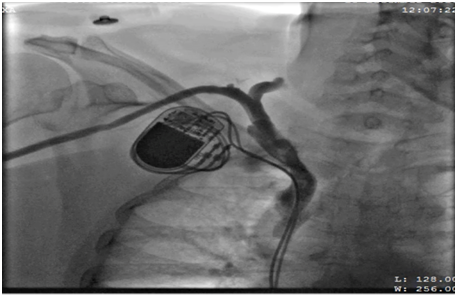

62 years old lady presented to the electrophysiology clinic with a history of shortness of breath, orthopnea, paroxysmal nocturnal dyspnea and lower limb swelling have started 3 weeks back. She denied any chest pain or syncope. She is known as HTN, IHD (S/P PCI to LAD 10 years ago), and History of Complete heart block (S/P DDDR pacemaker 6 years back). Previous LV function was normal (EF >55%, No significant valvular disease). On examination: She was conscious, oriented and vitally stable BP: 110/70 HR 70B/M, regular, RR: 22, Pso2: 96% on room air, T : 36.5, Congested neck vein observed, Chest: bilateral fine end in inspiratory basal crackles CVS: Normal S1, S2, no add sound or murmur Abdomen: Lax, soft, no masses Lower limb: Bilateral pitting edema ECG: well functioning paced rhythm; patient was diagnosed as new acute decompensate heart failure which was confirmed by ECHO showed: EF <35 %, with an impressive ventricular dyssynchrony, no significant valvular lesion, The patient was admitted in CCU as a case of ADHF (as a complication of RV pacing), was started on Ant failure treatment and the decision was taken to upgrade the DDDR TO CRTP. Then, Patient was driven in to Catha Lab. The procedure was initially attempted on the right, with successful cannulation of the right subclavian vein but unable to advance the guide wire to the superior vena cava (SVC), Venogram through the right anti-cubital vein showed a short occlusion of the right subclavian vein (Figure 1). The procedure was abandoned and LV lead implantation was performed on the left (Figure 2). Mild dissection of the coronary sinus occurred (Figure 3). Then sealed spontaneously and the LV lead was secured deeply in the posterolateral CS branch, a pair of long forceps were used for blunt dissection to create a subcutaneous tract from the right to the left. The proximal end of the LV lead was grasped with the forceps and tunneled above the sternum to rejoin the pocket (Figure 4). Then programming was done with good homeostasis.